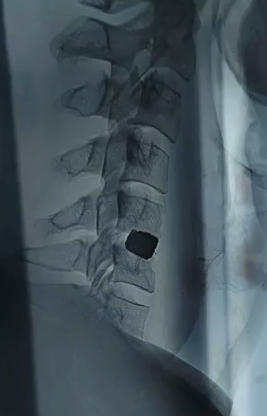

Здравствуй двачик, на прошлой неделе вышел из отпуска и уже дергается глазик, вчера сидел на работке пока поликлинику не закрыли и не все доделал. Не могу перестать кричать внутри головы! Потому мы с вами будем сегодня играть в доктора! Я буду вам показывать фоточки а вы угадывать пиздецомы! Што шпогнали! Найдите поломку!